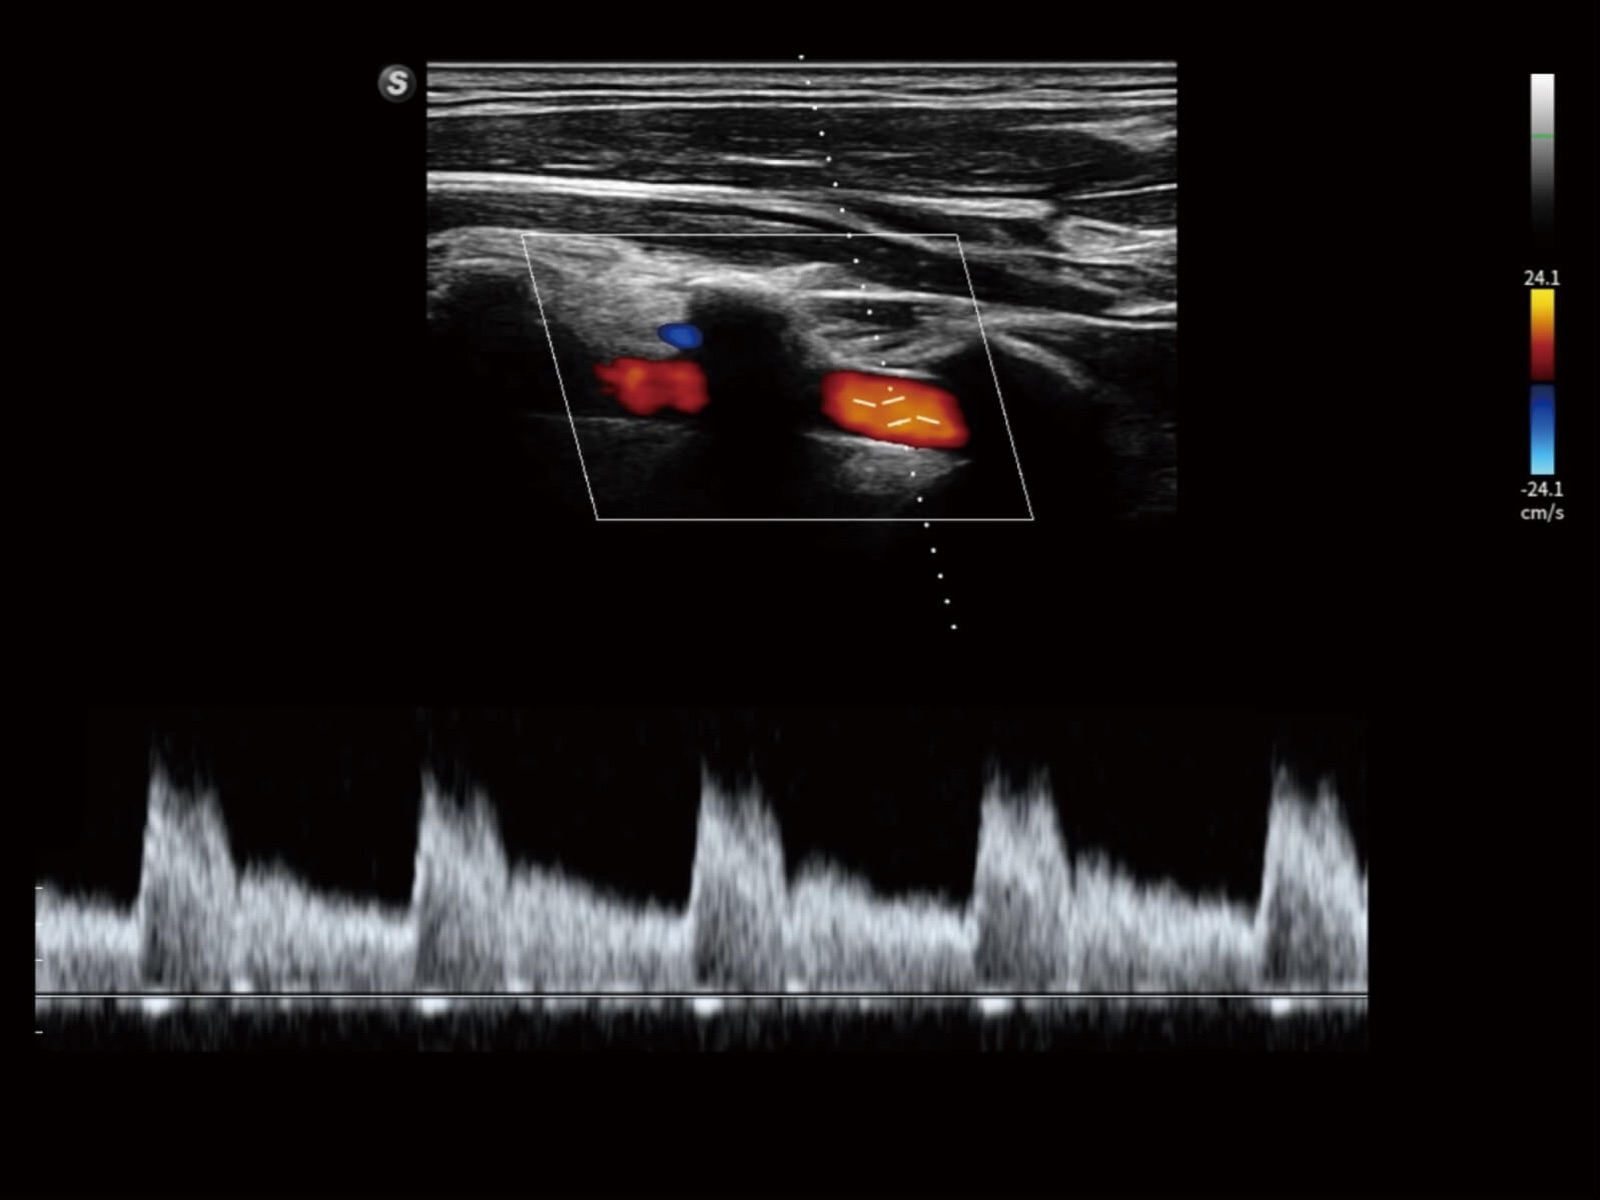

Bright Flow立体血流成像

通过光照模型,使二维血流显示出立体的效果,增加血流的敏感性、成束性,减少外溢。可以和其他不同的血流技术联合使用,轻松应对微小血管,增强血流的立体效果,提升视觉敏感性。